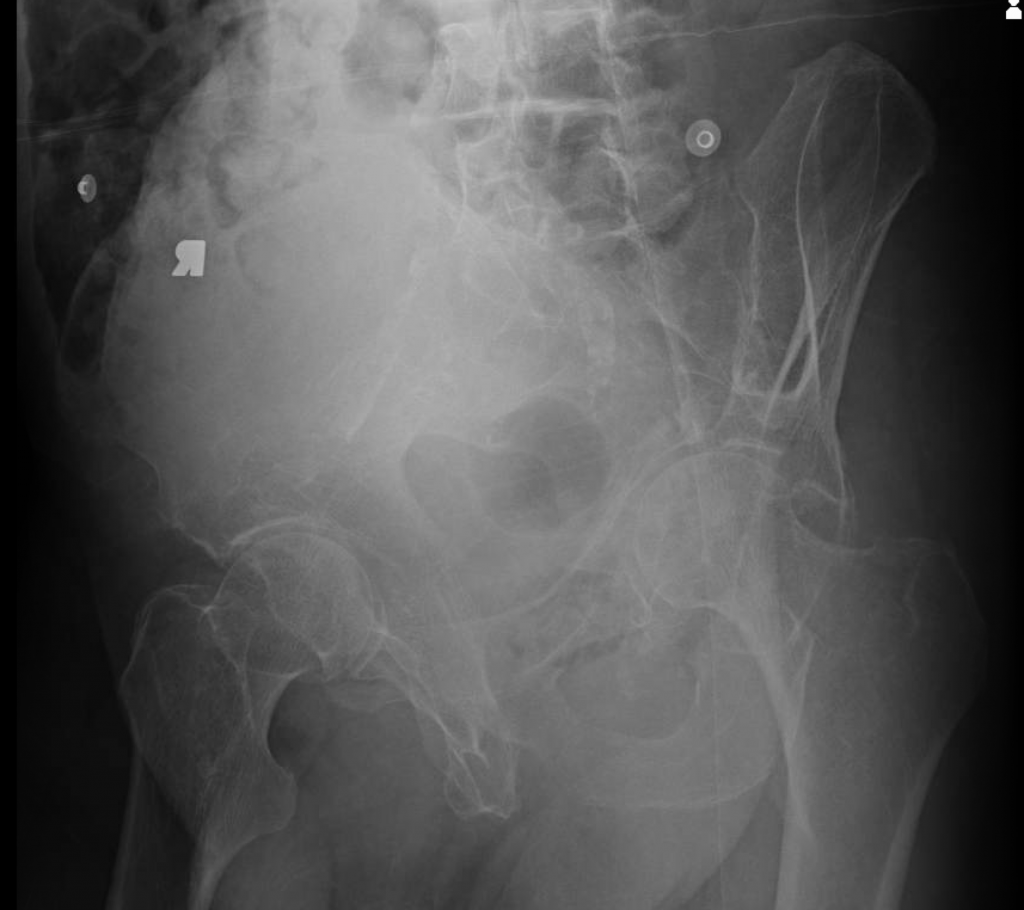

This is a 78 year old male who fell and sustained an anterior column acetabular fracture. The patient had a history of peripheral vascular disease and previously underwent femoral-femoral artery bypass. This precluded him from having a traditional open reduction internal fixation (ORIF) of the acetabulum through an ilioinguinal approach.

The patient underwent simultaneous acetabular ORIF and complex THA reconstruction by Dr. Darwin Chen and Dr. David Forsh (Chief of Orthopaedic Trauma). A Kocher-Langenbeck approach was used for exposure. The anterior and posterior columns were secured together using a single posterior-to-anterior screw just superior to the acetabulum. An acetabular shell was implanted with excellent inherent stability, followed by screw fixation into the superior dome as well as inferiorly into the ischium.